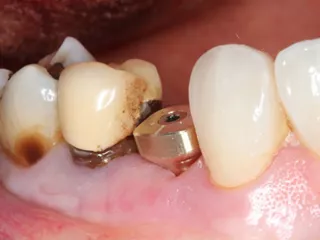

Dr Sami EL MASRI, Belgium The wide diameter selected from the Axiom® X3 implant range allowed us to treat this basic molar without large grafts. Patient care was optimal, and follow-ups show stability of solution. Read more